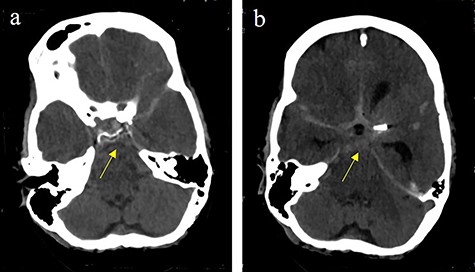

During the next days, the clinical status was stable. On the 43th post-operative day, the clinical situation worsened by an epileptic state with development of maximally dilated pupils without light reaction. CT revealed a massive bifrontal bleeding with rupture into the ventricles and brain herniation (Fig. 7). On the 44th post-operative day, brain death was diagnosed.

Bifrontal intracerebral bleeding with brain swelling and herniation: (a) coronal cCT, (b) axial cCT